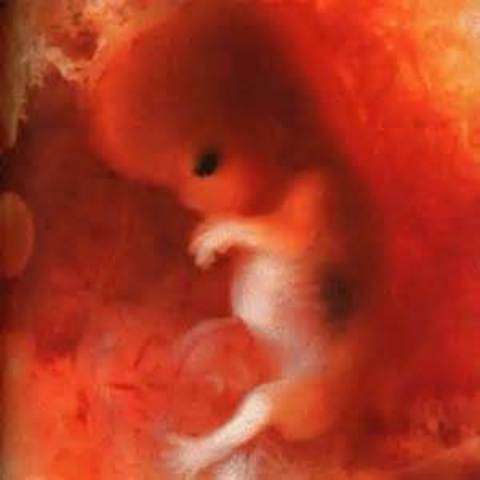

9 Weeks Pregnant

The baby is now about the size of a grape. All of the baby's body parts are formed and will continue to grow. The baby's teeth will begin to form over the next few weeks. Her eyes are fully formed. Event though her eyes are fully formed the eye lids are fused shut and will not open until 27 weeks. The baby's earlobes, nose, adn mouth are fully distinct now. The baby still weighs about a fraction of an ounce. In this week the baby is considered to be a embryo.